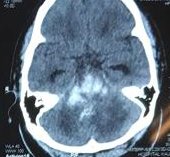

Pendarahan Dalam Otak

pupil fixed dilated Dr. sluggish. 6 mm bilaterally.

Intubated. not sedated. gcs macam kayu. body macam kayu.